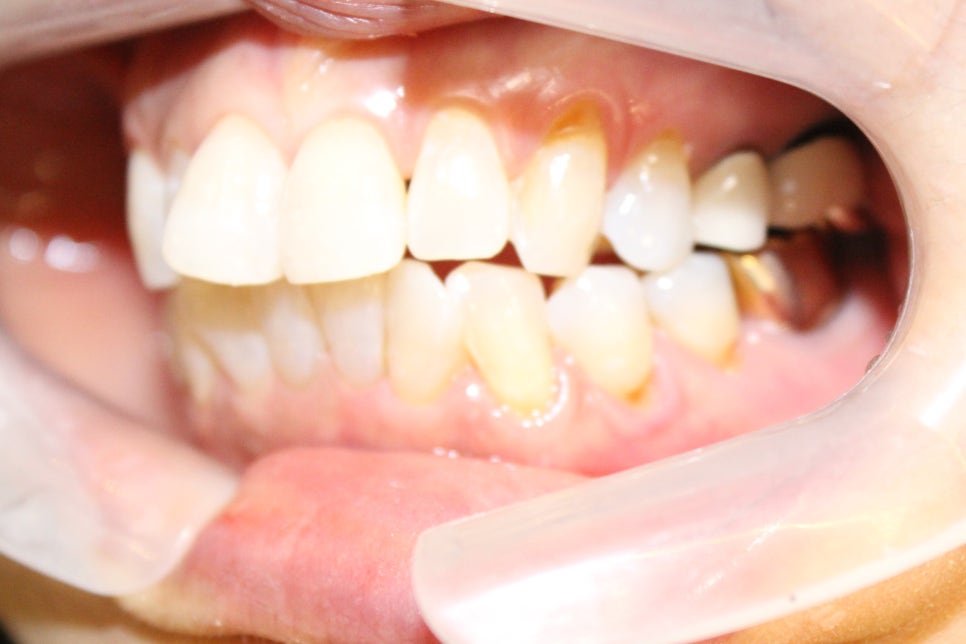

그래서 마스크 벗기 전 단시간에 걸쳐 앞니만 설측으로 빨리 간단하게

신논현역 치과 스마일 뷰에서 치아교정 한번 진행해 보시기를 권합니다.

벌어진 앞니나 비뚤어진 앞니, 토끼니, 덧니, 치아배열이 마음에 들지 않으셨던 분들이

아무도 모르게 감쪽같이 빠르게 진행할 수 있는 치아교정 방법이니까요.

우리가 거울 볼 때 계속 신경 쓰이는 곳 하나씩은 다 있으시지요?

약간 튀어나온 앞니, 조금 벌어진 앞니 치아 하나만 비뚤어져있거나 덧니가 있어서 있어서

마음 놓고 활짝 웃지 못하는 콤플렉스

신논현역 치과 스마일 뷰에서 진행하는 설측 부분교정은 교정이 필요한 치아 안쪽에만

장치를 붙여서 치아를 이동하는 방법이에요.